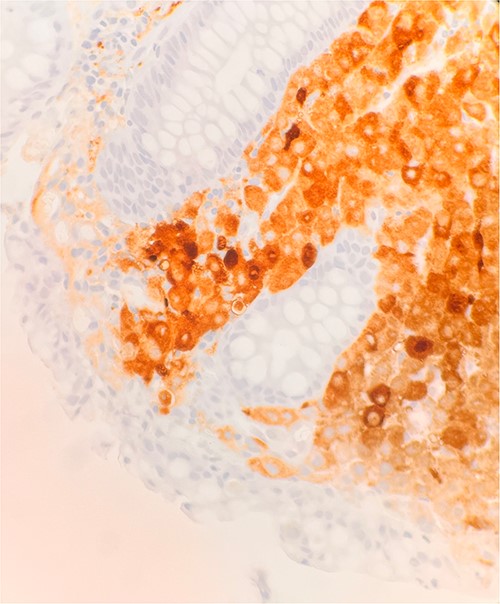

Microscopic examination shows extensive involvement of the bladder wall by sheets of small round blue tumor cells showing cleaved and irregular nuclear contours and conspicuous nucleoli. Mitotic activity is frequent and majority of cells show scant amphophilic cytoplasm with few foci showing more abundant bubbly cytoplasm and others with clear foamy cytoplasm (Fig. 1). A rare foci of finely granular brown pigment representing melanin and moderate cytological atypia in a small area of surface urothelium. Similar morphological features are seen in colonic biopsy specimens (Fig. 2).

Microscopic examination reveals sheets of round cell between unremarkable colonic crypts. H&E stain 40×.